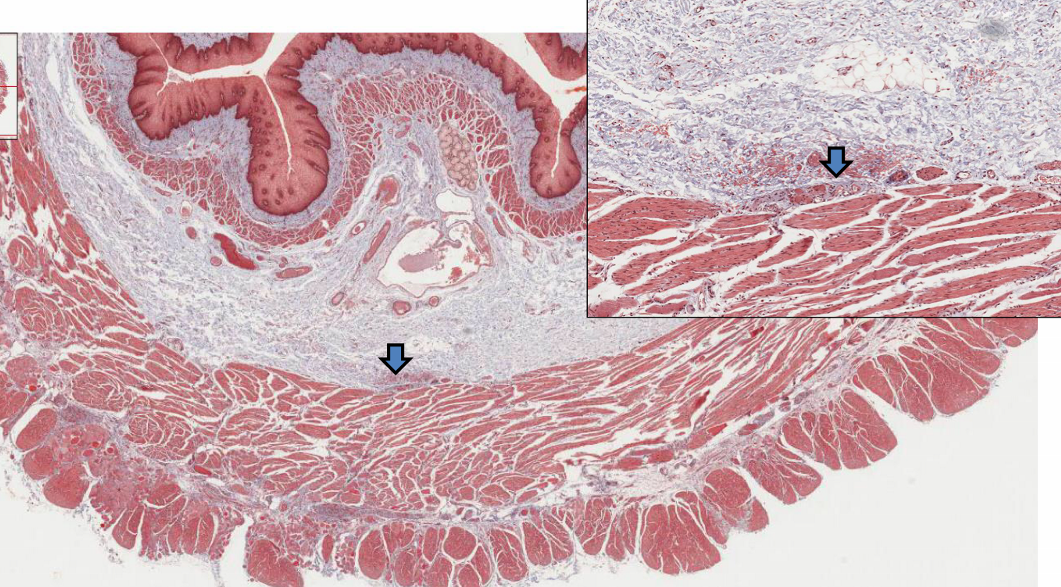

describe the rectoanal junction

* epithelium transitions from glandular intestinal epi. (simple columnar) to stratified squamous epi. (non-keratinized to keratinized)

describe congenital megacolon (Hirschspring disease)

* faulty migration of neural crest cells * lack of myenteric plexus * decreased peristaltic movements of the gut * dilated colonic segment